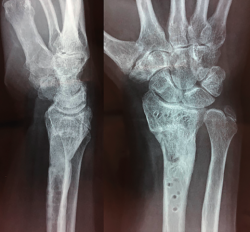

Figura 4. Aspecto final al mes de la retirada del material.

El paciente requirió extracción de la placa por tenosinovitis de los flexores al año de la segunda cirugía (Figura 4). La exploración final, al mes de la retirada del material, comprobó un balance activo de los arcos de movimiento: extensión 40°, flexión 60°, desviación radial 20°, desviación cubital 40° y pronosupinación completa. Balance muscular de 4/5, cierre completo del puño y pinza oposición completa.